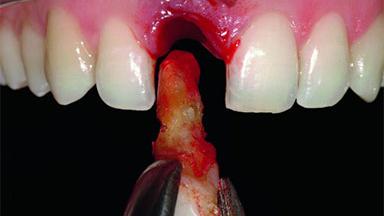

Replacement of an Upper Right Central Incisor with Root Resorption: Ridge Preservation, Delayed Placement of an NC Bone Level Roxolid Implant

A 32-year-old female Caucasian patient with a compromised maxillary right central incisor was referred to us by a general dentist. Her chief complaints were discomfort and mobility of tooth 11 with unsatisfactory esthetics due to discoloration. The patient reported a previous trauma, some years earlier, as the origin of pathology on the afflicted tooth. Anamnesis was negative for any other dental or periodontal pathology in the remaining dentition. The patient did not take any medication and reported to be a light smoker (5–10 cigs/day). She had high esthetic expectations of her treatment. The extraoral examination revealed a high smile line with full exposure of her maxillary teeth and surrounding soft tissue in the area between the second premolars.

Bone Volume Deficient horizontally, requiring prior grafting